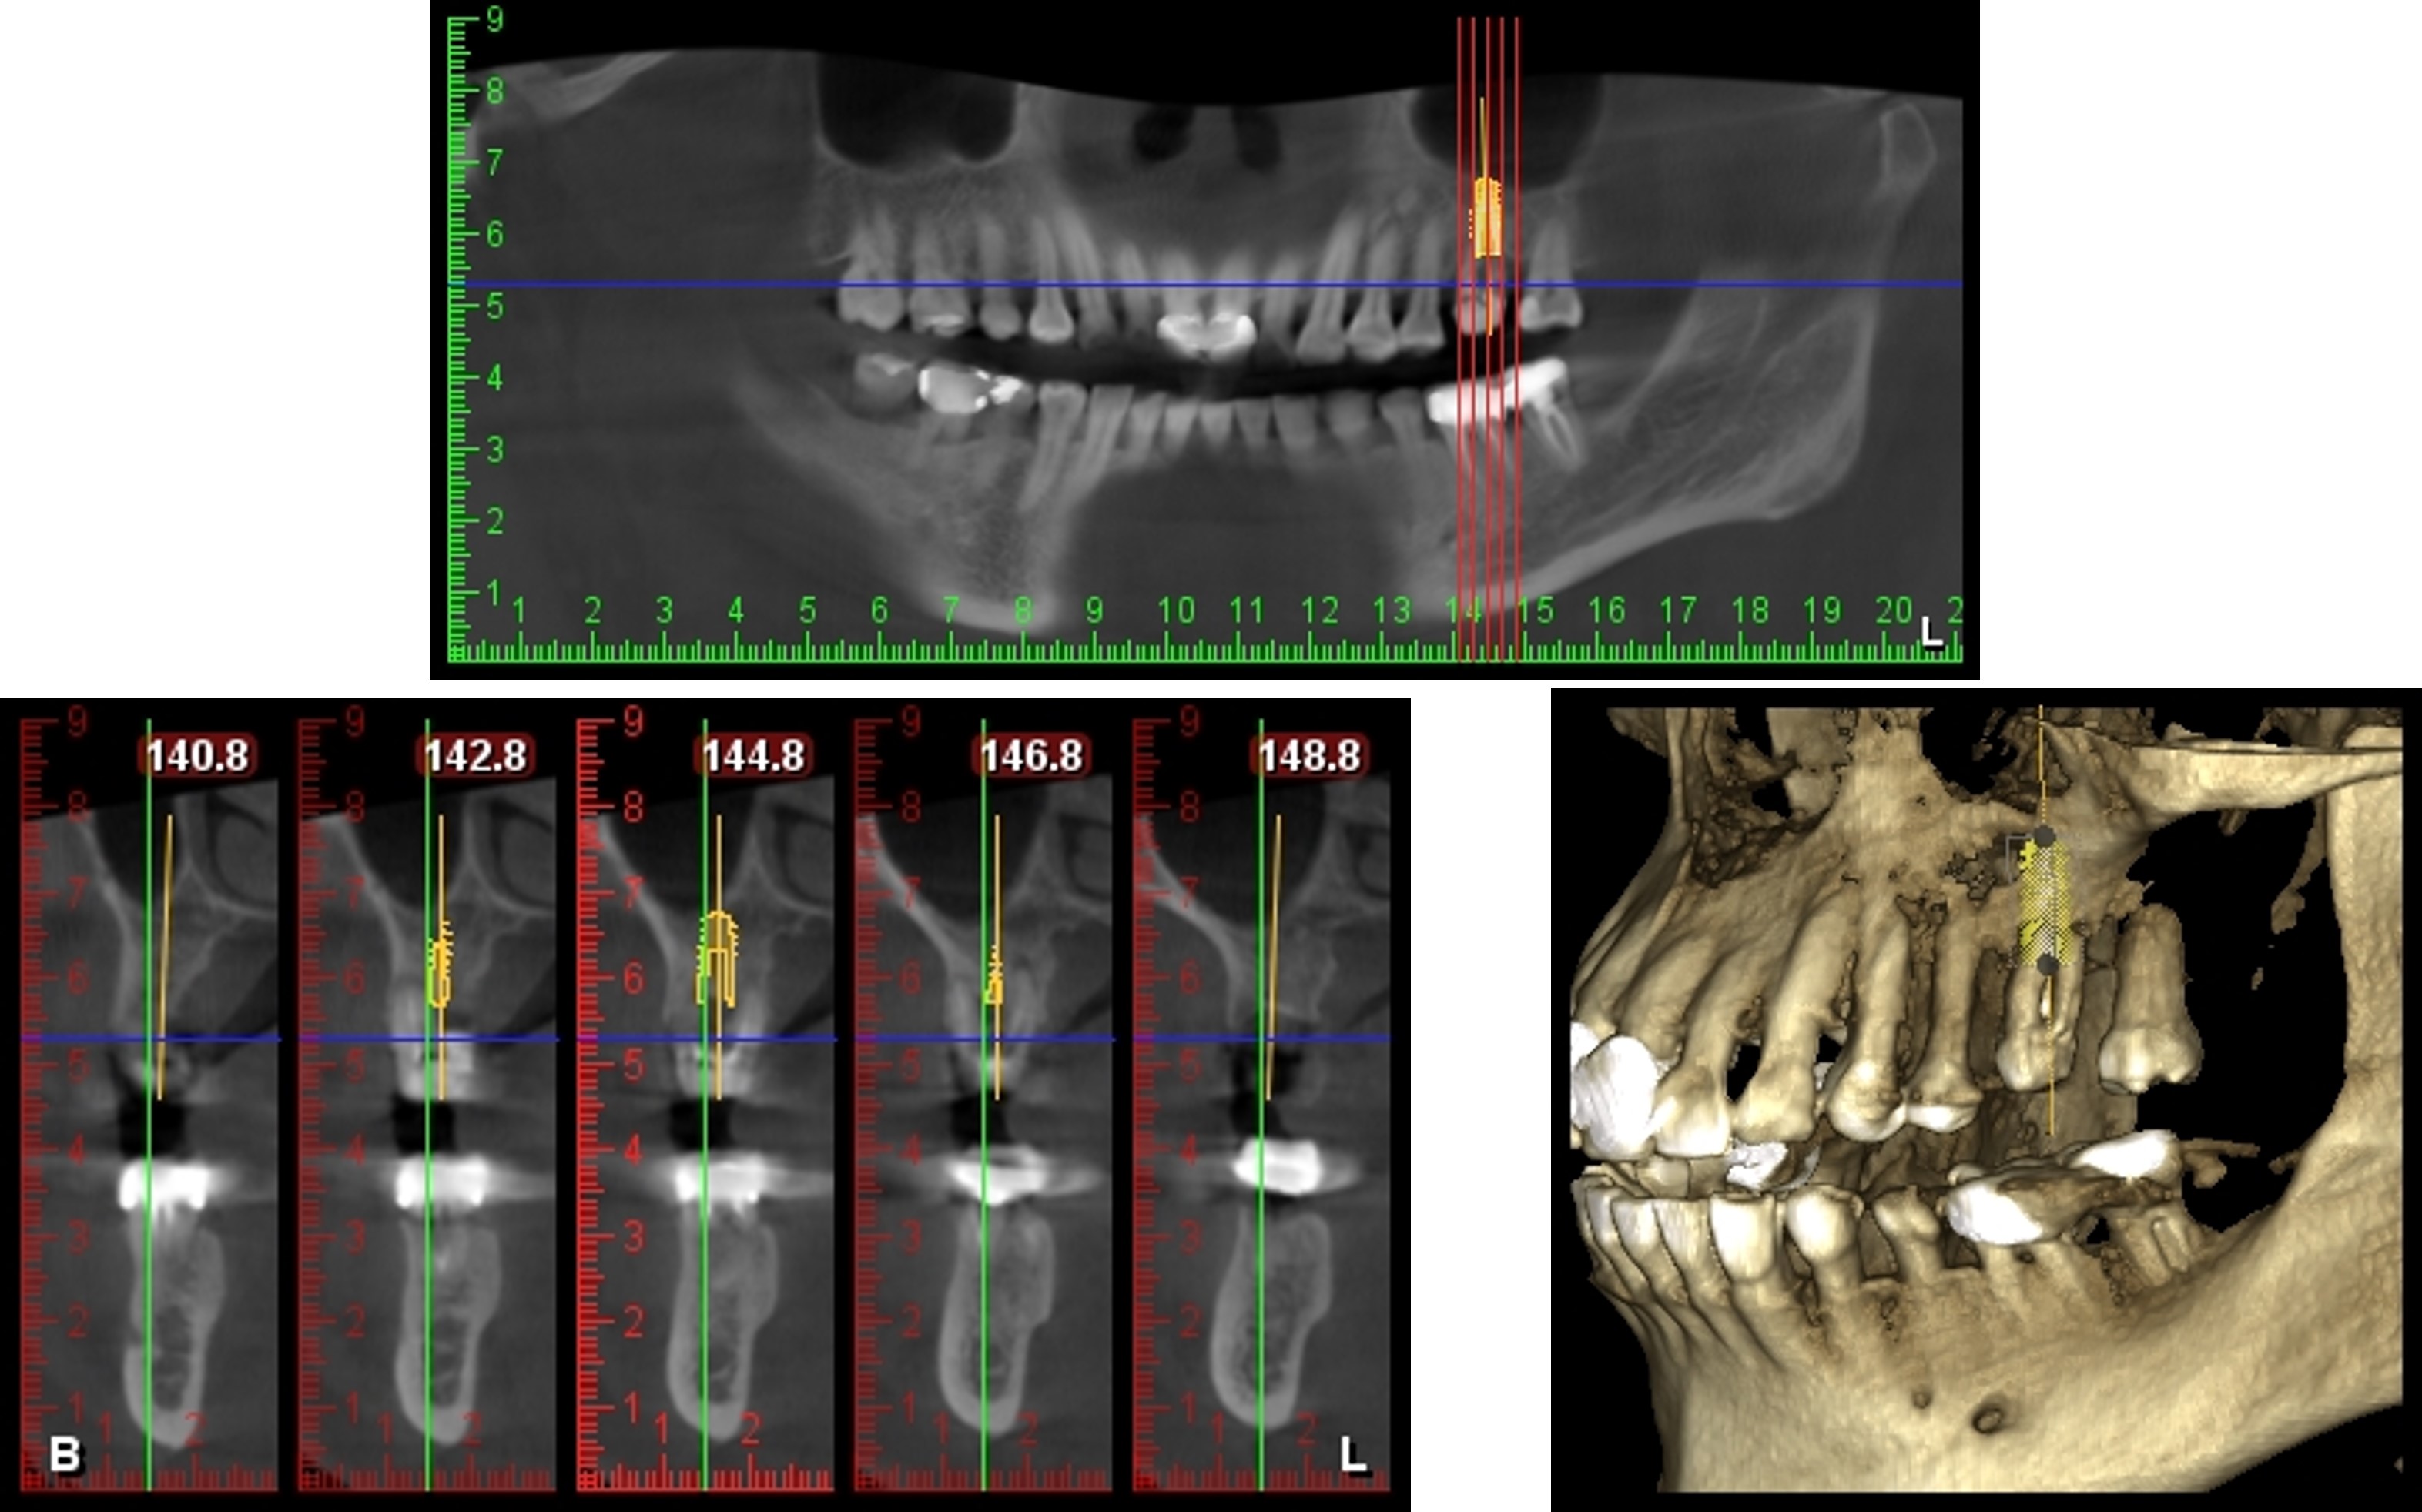

拔牙前植牙規畫模擬

植牙、補骨及補骨

植牙後,角度良好